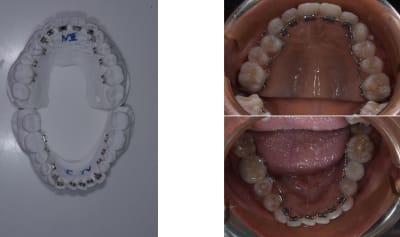

Et c'est revenue du labo en fin de journée.

L'impression 3D du set up final ( sert de modèle pour plier le file )

Le tray pour impression indirecte. Ici j'utilise un gel siliconé transparent qui est super pour les 2D .

Le truc le plus chronophage c'est de faire le set up 3D car il faut faire des mouvement réalistes. Le tray se fait en 5 minutes .

Et voilà collé ce matin.

Pour Adhoc tu observeras qu'il y a quatre couronne céramique en bouche et aucun soucies.

Lors de l'insertion du fil j'ai un peut bourriné et un bracket c'est décoller mais c'était au niveau d'une canine. Vue qu'il y a une base en résine adapté à l'anatomie de la dent , repositionner le bracket en bouche ne pose pas de soucie.